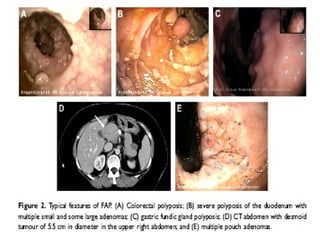

POLIPOSIS ADENOMATOSA

FAMILIAR Pólipos adenomatosos > 100

 Trastorno hereditario autosomico dominante. Penetrancia

del 100%.

 80% hay antecedentes familiares.

 10-30% mutaciones nuevas.

 1/10000 nacidos vivos.

 Causa el 1% de CCR.

 Edad promedio en detectar los pólipos es 15 años.

 15% evidencia de pólipos a los 10 años.

 75% evidencia a los 20 años.

 90% evidencia a los 30 años.

 El CCR. Aparece en promedio a los 35 años.

 Los pólipos pueden tapizar toda la superficie del epitelio colorrectal en

casos severos y dejar indemne algunas porciones del epitelio.

 La mayoría mide menos de 5 y 10 mm.

 El hallazgo de uno o más pólipos de más de 1 cm. se asocia a 47 % de

padecer CCR.

 La mayoría de PAF. Presentan CCR. de localización izquierda o distal.

 La frecuencia de neoplasias sincrónicas o metacrónicas es

elevada..colectomía total.